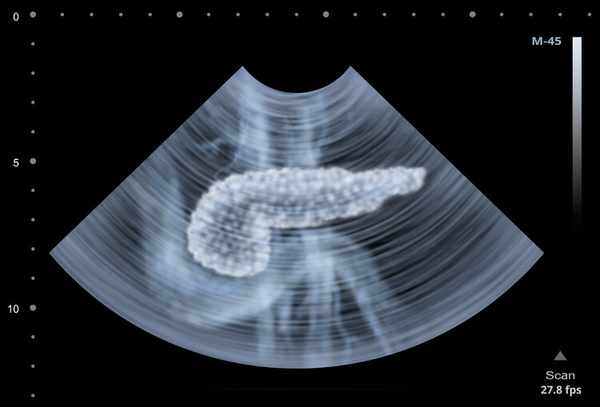

腹部CT檢查提示胰腺出現明顯水腫,有廣泛炎性滲出;甘油三酯高達74.93mmol/L(正常值的44倍),脂肪酶1522U/ml,確診為急性高脂性胰腺炎。

通常情况下,首先要做上腹部磁共振(MRI)和上腹部CT增强檢查,明確胰腺是否充血、水腫或出血。其次,要做超聲檢查,明確膽總管或膽囊的結石情况。